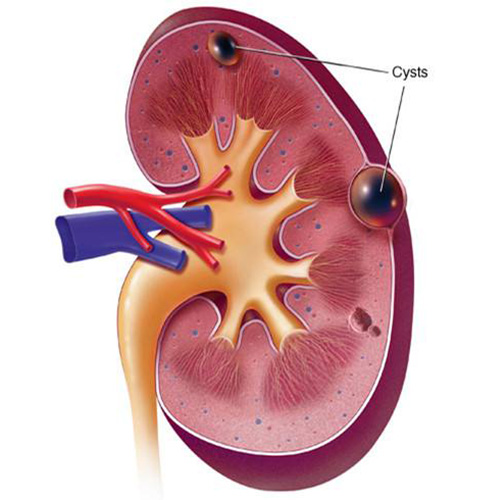

腎囊腫表現圖

腎囊腫的症狀

腎囊腫與正常腎對比

腎囊腫

A:多發性腎囊腫是多個獨立的腎囊腫,腎囊腫是由腎小管管壁囊狀擴張或者微小突出所形成,是成年人腎臟最常見的一種結構異常。腎囊腫可以為單側或雙側腎臟發生,也可發生一個或者多個,一般直徑在2cm左右。隨著年齡增長,腎囊腫發生率越來越高,30-40歲單……

A:腎囊腫指的是良性腎囊腫,也叫單純性腎囊腫,一般沒有明顯症狀,只有當囊腫體積比較大,壓迫而引起血管病變或者是尿路梗阻時,可能會出現相應的臨床表現,常見的症狀如下:1、血尿:如果當腎囊腫出現感染或者出血的時候,可能會有相關的症狀發生。如果腎囊……

A:腎囊腫臨床的症狀和表現根據具體情況要做分析,腎囊腫也有大有小,侷限性孤立性腎囊腫,或者瀰漫性多發性腎囊腫臨床情況迥然不同。前者對腎功能不會造成影響,大部分小孩都是通過B超、CT影像學的檢查發現。瀰漫性多發性腎囊腫引起腎臟的腫大,腎背膜受到壓……